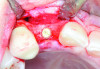

Fig 12 through Fig 14. Example of increasing MT with a roll technique. Fig 12: incision design for implant placement with a healing abutment placement and to enhance MT; the recipient site is prepared on the buccal side; the palatal aspect of the flap will be rolled to the buccal recipient site; Fig 13: insertion of roll of tissue taken from the palatal aspect of the flap; Fig 14: implant placement with healing abutment.